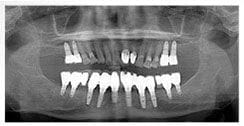

X 光片

術後X光片